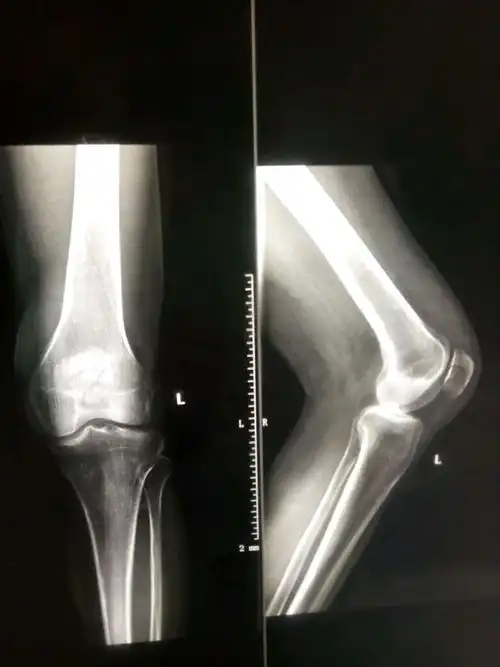

髌骨正侧位x线可确诊.对可疑髌骨纵行或边缘骨折,须拍轴位片证实.